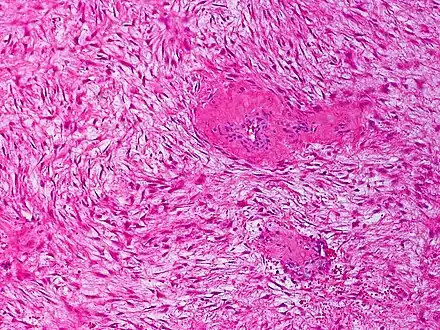

Desmoid fibromatosis, H&E stain. Banal fibroblasts infiltrate the adjacent tissue in fascicles. Mitoses may be infrequent.

Desmoid fibromatosis, H&E stain. Banal fibroblasts infiltrate the adjacent tissue in fascicles. Mitoses may be infrequent.

Histologically they resemble very low-grade fibrosarcomas,[3] but they are very locally aggressive and tend to recur even after complete resection. There is a tendency for recurrence in the setting of prior surgery; in one study, two-thirds of patients with desmoid tumors had a history of prior abdominal surgery.[4]